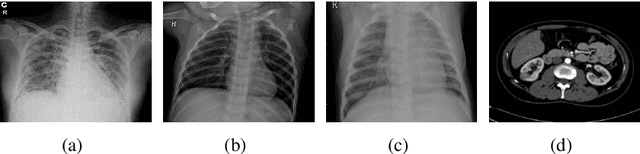

Over the years, the paradigm of medical image analysis has shifted from manual expertise to automated systems, often using deep learning (DL) systems. The performance of deep learning algorithms is highly dependent on data quality. Particularly for the medical domain, it is an important aspect as medical data is very sensitive to quality and poor quality can lead to misdiagnosis. To improve the diagnostic performance, research has been done both in complex DL architectures and in improving data quality using dataset dependent static hyperparameters. However, the performance is still constrained due to data quality and overfitting of hyperparameters to a specific dataset. To overcome these issues, this paper proposes random data augmentation based enhancement. The main objective is to develop a generalized, data-independent and computationally efficient enhancement approach to improve medical data quality for DL. The quality is enhanced by improving the brightness and contrast of images. In contrast to the existing methods, our method generates enhancement hyperparameters randomly within a defined range, which makes it robust and prevents overfitting to a specific dataset. To evaluate the generalization of the proposed method, we use four medical datasets and compare its performance with state-of-the-art methods for both classification and segmentation tasks. For grayscale imagery, experiments have been performed with: COVID-19 chest X-ray, KiTS19, and for RGB imagery with: LC25000 datasets. Experimental results demonstrate that with the proposed enhancement methodology, DL architectures outperform other existing methods. Our code is publicly available at: https://github.com/aleemsidra/Augmentation-Based-Generalized-Enhancement